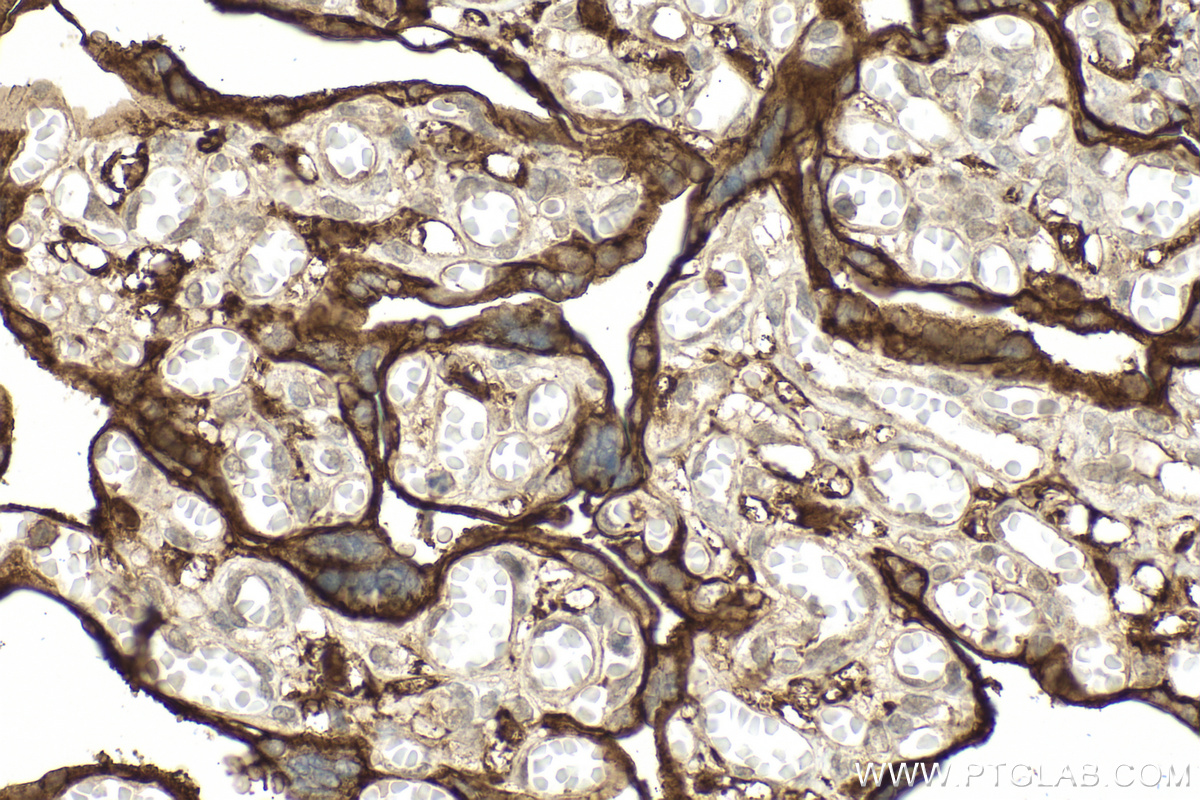

| Positive IHC detected in | human placenta tissue Note: suggested antigen retrieval with TE buffer pH 9.0; (*) Alternatively, antigen retrieval may be performed with citrate buffer pH 6.0 |

| Immunohistochemistry (IHC) | IHC : 1:200-1:800 |

15193-1-AP targets CD98/SLC3A2 in WB, IHC, IF/ICC, IP, CoIP, ELISA applications and shows reactivity with human samples.

CD98 is a cell-surface heterodimer consisting of a heavy chain (CD98hc) and a light chain. CD98hc also interacts with certain integrin b-subunits to regulate cell migration, survival, proliferation, and adhesion/polarity. CD98hc is overexpressed on the cell surface of many cancers and increased CD98hc expression is associated with the development and progression of tumors.(PMID:25084765). This protein has 4 isoforms with the molecular mass of 58-71 kDa and can be detected 85-94 kDa due to glycosylation. The glycosylated CD98hc can links to a non-glycosylated light chain (~40 kDa) via a disulfide bond to form a heterodimeric CD98 antigen with molecular mass of 120-130 kDa (PMID: 14770309).